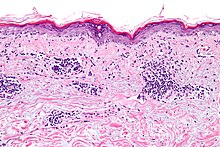

As many as 70% of people with lupus have some skin symptoms. The three main categories of lesions are chronic cutaneous (discoid) lupus, subacute cutaneous lupus, and acute cutaneous lupus. People with discoid lupus may exhibit thick, red scaly patches on the skin. Similarly, subacute cutaneous lupus manifests as red, scaly patches of skin but with distinct edges. Acute cutaneous lupus manifests as a rash. Some have the classic malar rash (commonly known as the butterfly rash) associated with the disease.[14] This rash occurs in 30 to 60% of people with SLE.[15]

Discoid (cutaneous) lupus is limited to skin symptoms and is diagnosed by biopsy of rash on the face, neck, scalp or arms. Approximately 5% of people with DLE progress to SLE.[56]